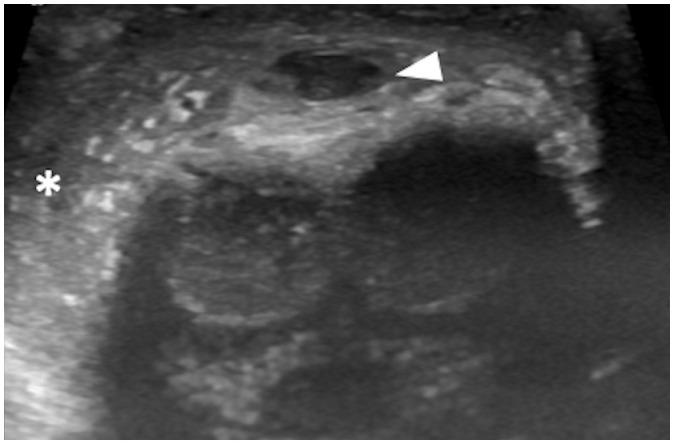

Penile emergencies are uncommon and can be categorized as having infectious, vascular, traumatic, or multifactorial etiologies. To facilitate early diagnosis and treatment during emergency, US and color Doppler imaging are imperative. US depicts hypoechoic collections regardless of the presence of air foci in infections like abscess and Fournier's gangrene. Color Doppler imaging is conducted to evaluate vascular conditions such as penile Mondor disease (PMD) and priapism. PMD is indicated by the absence of color flow and non-compressibility of dorsal penile vein. Priapism can be categorized based on cavernosal artery flow: high flow and low flow. In traumatic injuries like penile fracture, US reveals breach in tunica albuginea with hematoma. Peyronie's disease can be multifactorial in origin and the imaging is commonly visualized as thickening of the tunica albuginea and echogenic calcified plaques. Urethral injuries are urethral discontinuity with adjacent collection. Urethral calculus is visualized as echogenic focus with posterior acoustic shadowing. Therefore, effective collaboration between radiologists and urologists is required for appropriate initial diagnosis and prompt treatment.

阴茎急症并不常见,可分为感染性、血管性、创伤性或多因素病因。为便于在急诊时进行早期诊断和治疗,超声(US)和彩色多普勒成像必不可少。在诸如脓肿和福尼尔坏疽等感染中,无论是否存在气灶,超声均能显示低回声液性聚集。进行彩色多普勒成像以评估血管状况,如阴茎蒙多氏病(PMD)和阴茎异常勃起。阴茎蒙多氏病表现为阴茎背静脉无血流信号且不可压缩。阴茎异常勃起可根据海绵体动脉血流分为:高流量型和低流量型。在阴茎骨折等创伤性损伤中,超声显示白膜破裂并伴有血肿。佩罗尼氏病的病因可能是多因素的,影像学表现通常为白膜增厚和回声增强的钙化斑块。尿道损伤表现为尿道连续性中断并伴有相邻液性聚集。尿道结石表现为伴有后方声影的回声增强灶。因此,放射科医生和泌尿外科医生之间需要有效协作,以进行恰当的初步诊断和及时治疗。